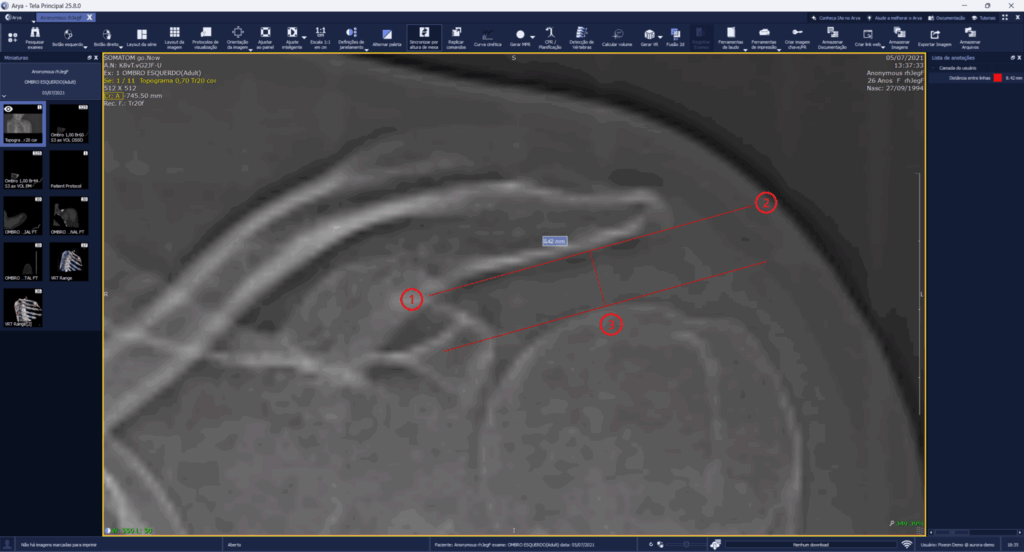

The new Distance Between Lines tool allows users to draw two parallel lines and measure the spacing between them, making it valuable for verifying acromiohumeral, acromioclavicular, and intra-articular knee distances, among others.

Focused on generating greater efficiency in image analysis, the calculation is performed with just three clicks: the first two define the start and end of the first line, and the third defines the position of the second line, recording the effective distance between the two.